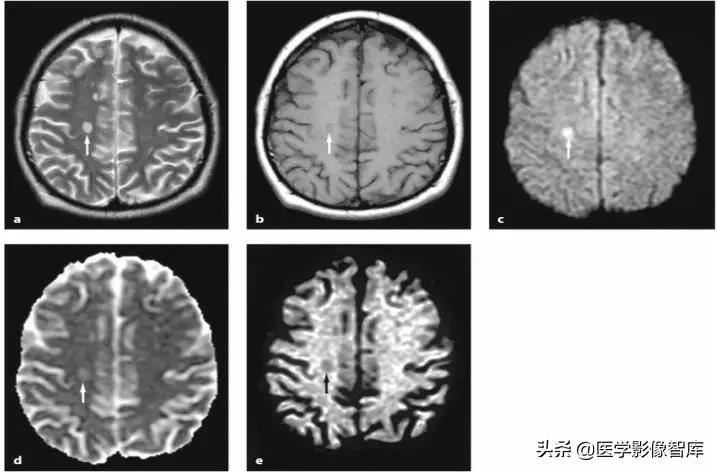

线粒体脑肌病是一组累及多系统的复杂疾病,伴有广泛的生化和遗传缺陷。线粒体脑肌病伴高乳酸血症和卒中样发作(MELAS)是研究相对较多的一类线粒体脑肌病。卒中样发作是 MELAS 的主要临床特征。尽管 MELAS 卒中样发作常在病程早期快速而完全的恢复,可是一旦第一次卒中样发作发生,患者的神经功能状态会持续恶化。卒中样发作在临床上可表现为多种神经系统症状,如癫痫发作、头痛、意识状态改变、局灶性无力、视力下降、感觉缺失、构音障碍和共济失调。典型的 MELAS 磁共振病变多分布在皮质和皮质下白质,深部白质不受累,表现为 T2WI、DWI 高信号类似卒中样表现。磁共振波谱可检测到梗死灶及其他脑部未受累区域中乳酸的存在。典型磁共振表现如图 4 所示。

图 4 MELAS 患者,A 为 DWI,可见皮层 / 皮层下 DWI 高信号,B 为 ADC 图,可见病灶低信号,C 为 FLAIR,可见病灶高信号,D 为该患者的慢性期 FLAIR,可见病灶几乎消失,受累部分脑策划萎缩